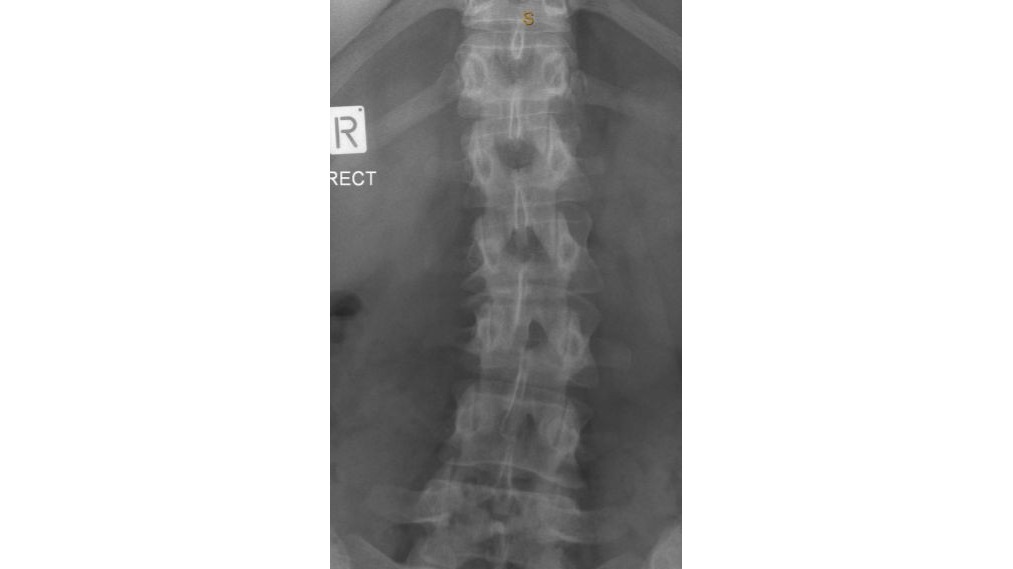

Hello my name is Krista Bain When I was a teenager I was in a incident where I came of a sprinting horse. The horse flwe me in the air and I landed crash down on my back with a 'crunch' sound in my spine. I felt tingling in my legs and adrenaline kicking in. I was so afraid. I was in shock unable to get up or move. I waited what felt to hours pass by and managed to slowly grasp myself to a stand. When I arrived back to to the horse stable I told the people there what happened. They comforted me and let me call my caregiver( I will not make the person to there discression)They knew the horse I was riding was not tame as did I but I regretfully chose to ride this horse regardless.I was instructed to go to hospital and tell my caregiver to take me there.The drive was around 45 mins from home and longer to the hospital Because I had come off horses many many times in the past my caregiver decided to make the decision not to take me to the hospital to be examined. I was in alot of pain stopped riding and took weeks off school. Because of this eventually my caregiver took me to a medical centre but when I spoke she downplayed what I said out of embarrassment of not providing my care at the time and I left that appointment deviated and without any Acc claim or examination. I have finally received a doctor after many attempts for x-rays that went unnoticed be ause I didn't receive a claim to begin with. The x-ray shows L2 &L1 fractures that have healed and a concaved scelrosis of the lower spine. The pain has only gotten worse over the years and without nerve pain killers 5 times per day I'm in absolute agony. I am afraid to take these pills for the rest of my life. I am unable to receive any help for surgery from Acc because this is a past incident. I have not been able to keep any work because my pain get heightened with any form of physical work. I am afraid of ending up in a wheelchair when I am older and having to take nerve painkillers for the rest of my life. I have a six year old son and I really cannot bare the thought of the future going downhill like this. I am afraid of being stick for the rest of my life due to the neglect of my caregiver. I have big dream to accomplish I have a great voice, I was a champion at netball and I love animals horseriding and travel. I feel down and out and the pain is closing off my ability to speak up and to get out and do things I would usually enjoy. I want to be a great role model for my son and work a great deal and provide the life for myself and my son so he can have a good future as well. I need to raise $21,000 for a lower spinal infusion surgery to be able to get this done. I would greatly appreciate any help and I thankyou ? Krista